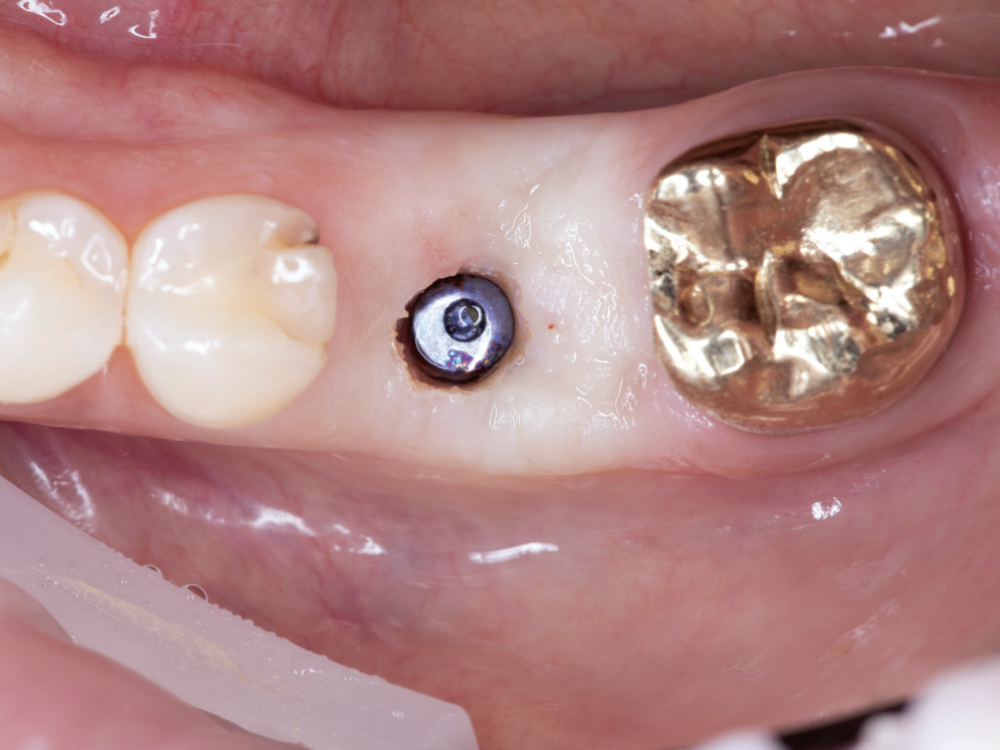

Implant post scan on left side of mouth

Implant post scan pointing down

Implant post scan close up

Verify the Scans Before Dismissing the Patient. Review all critical areas while the patient is still in the chair, ensuring complete scan body capture, accurate contacts, adequate tissue detail, and proper bite registration. Zoom in on critical areas to verify resolution and completeness. It takes only two minutes to verify a scan, but potentially days before a patient is able to return to your practice. Use the scanner’s analysis tools to identify distortions or artifacts.

Don’t Trust Your Scan Without Verification. Screen visualization during scanning does not guarantee complete data capture, and small gaps, artifacts, or distortions may not be evident during active scanning. Discovering scan deficiencies after the patient leaves wastes everyone’s time. Make verification a non-negotiable final step at every scanning appointment.